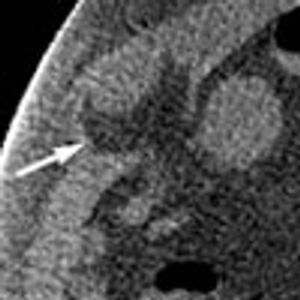

A 50-year-old man with type 2 diabetes mellitus and hypertension presented to the emergency department with abdominal pain and vomiting of 2 days' duration. He denied fever and urinary symptoms.